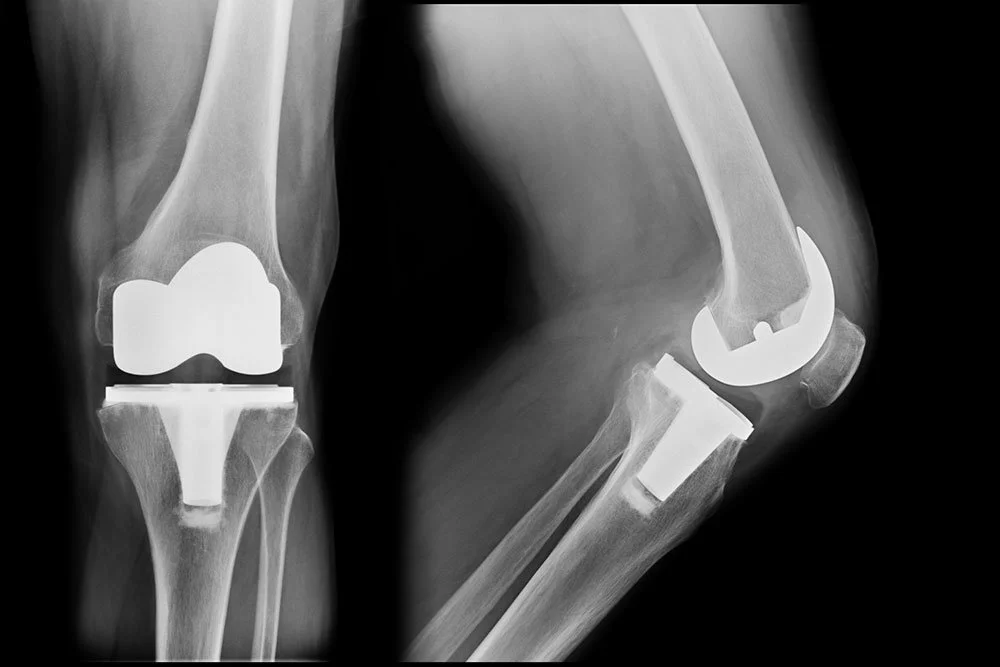

Knee Replacements

What is a Knee Replacement?

Knee replacements are typically recommended for patients with arthritis or other knee disease and injuries. When these conditions have not responded to nonsurgical treatments - such as steroid injections and over-the-counter anti-inflammatory medications - knee implants are designed to relieve the pain caused by these issues. A total knee replacement lasts an average of 20 years.